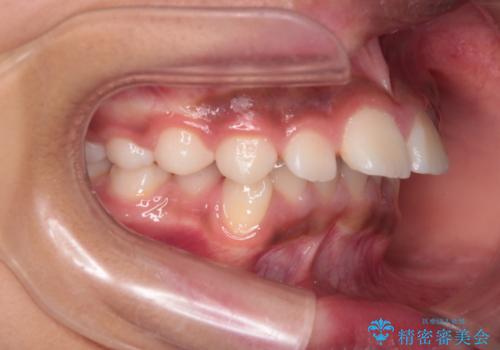

- 患者様は前歯の突出を主訴に来院されました。診査の結果、上顎の前歯が前方に傾斜しており、口元がやや突出して見える状態でした。一般的にこのようなケースでは抜歯矯正が選択肢となりますが、**患者様が抜歯を希望されなかったため、非抜歯での遠心移動(奥へ動かす治療)を計画しました。そのため、リンガルアーチ(歯の裏側に装着する装置)とTAD(歯科矯正用アンカースクリュー)**を併用し、上顎の歯を後方へ移動させながら噛み合わせを整える方法を選択しました。

まず、上顎にリンガルアーチを装着し、歯列の幅を適正に維持しながら遠心移動をサポート。さらに、**TAD(矯正用アンカースクリュー)**を利用することで、奥歯を固定源とせずに前歯だけを後方へ移動させることが可能になりました。これにより、抜歯をせずに前歯の突出を抑え、バランスの取れた口元へと改善。治療後、患者様からは「抜歯せずに理想の仕上がりになり、大満足」とのお声をいただきました。